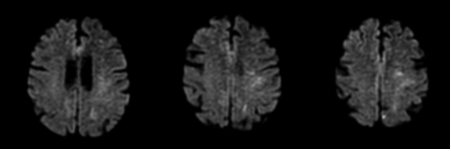

病例2:66岁女性患者,吸烟,既往高血压病史。因突发右侧眼眶周围疼痛、畏光和看到漂浮物而收治入院。头颅CT提示前纵裂SAH。次日DSA未见颅内血管异常,左侧颈内动脉近端可见粥样硬化斑块引起90%以上狭窄。6小时后,患者突然出现失语,头颅MRI-DWI图像显示左侧大脑中动脉供血区多发弥散受限病灶,提示左侧颈内动脉斑块脱落引起的继发性血栓栓塞。患者给予口服阿司匹林治疗,次日行左侧颈动脉内膜剥脱术,术后患者恢复顺利。

图2. A、B. 头颅CT示前纵裂局灶性SAH,大脑前动脉动脉瘤可疑;C-F. DSA显示左颈内动脉近端粥样硬化所致高度狭窄(C),但未发现颅内动脉瘤和血管畸形(D-F);下面两排图像为头颅MRI-DWI相,示左大脑中动脉供血区多发弥散受限病灶。